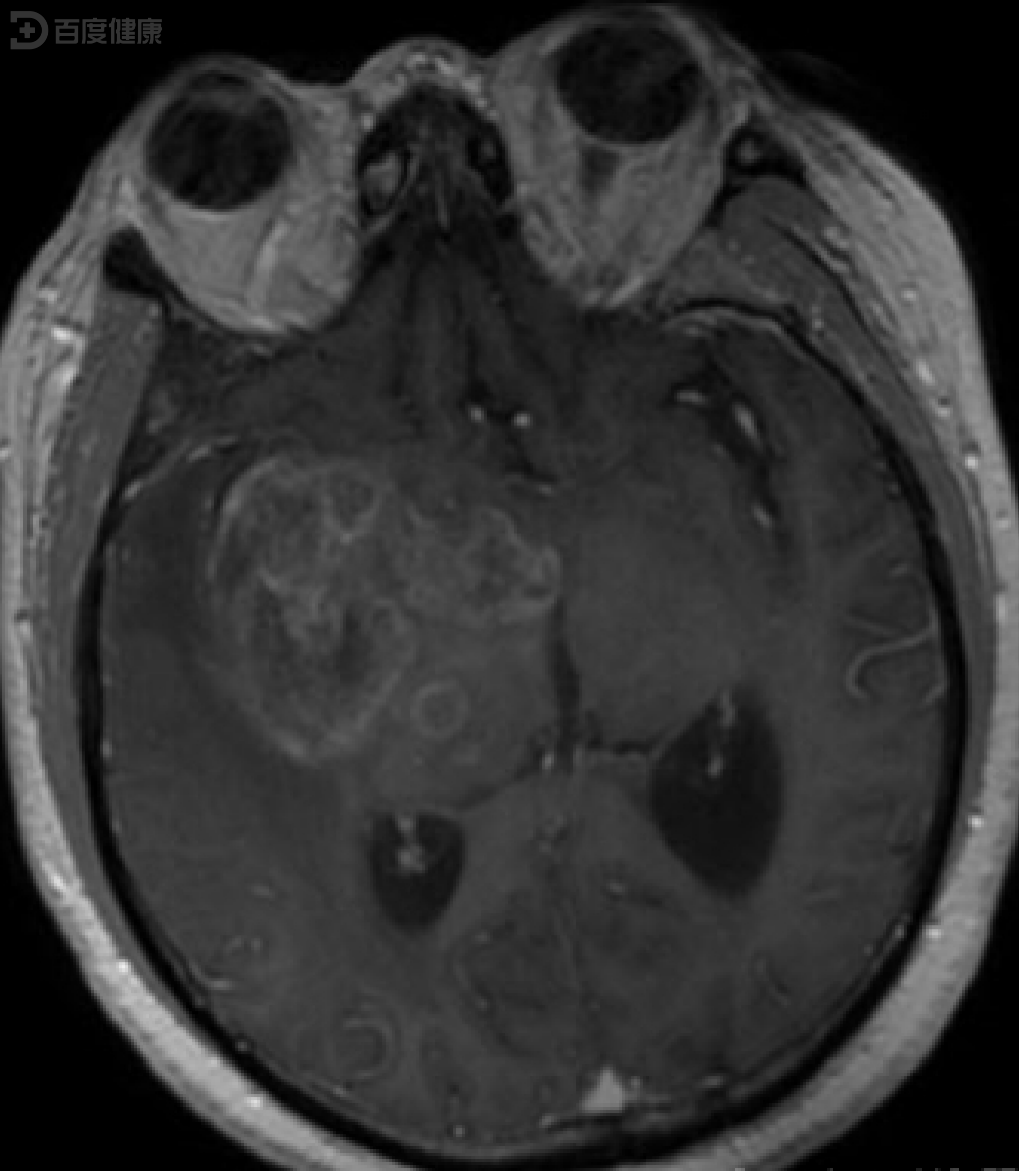

术后病理提示:弥漫性间变性星形细胞瘤,伴大脑胶质瘤病生长方式.